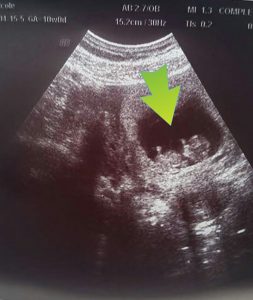

This is Chanel’s ultrasound at 4weeks.. As you can she had the image of a kidey bean but they grow so much every week.. Watch in the other ultrasounds how fast they develop